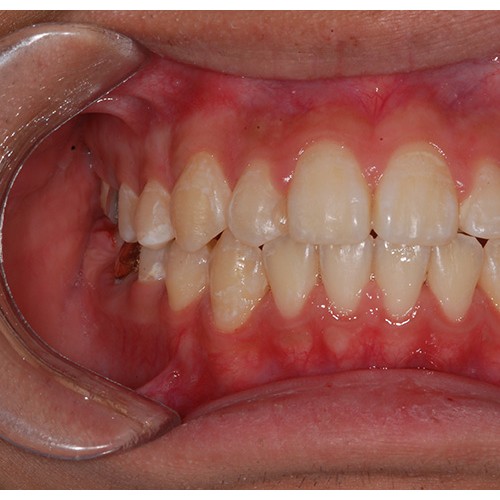

CHUNCHU'S ORTHODONTIC CLINIC# BEFORE_AFTER

춘추치과교정과를 방문해주신 분들의전후 사진을 확인해보세요.